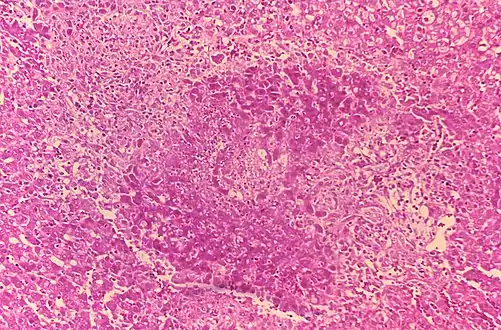

3. Histologic evidence of granulomatous hepatitis on hepatic biopsy